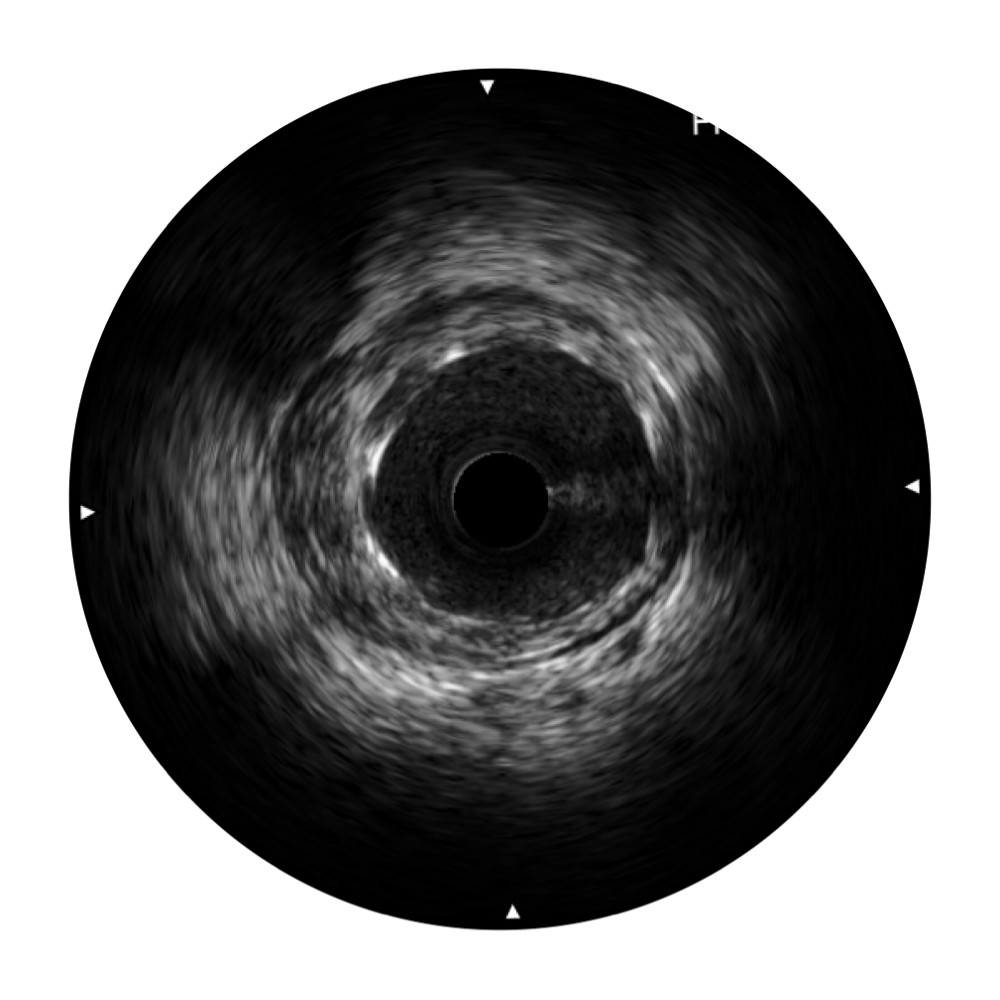

db真人体育官网宽频IVUS图像

对比传统IVUS导管成像,db真人体育官网宽频IVUS图像的近场支架梁显影更细腻,远场中膜外血管仍清晰可辨,兼顾远中近,兼顾分辨力与穿透深度